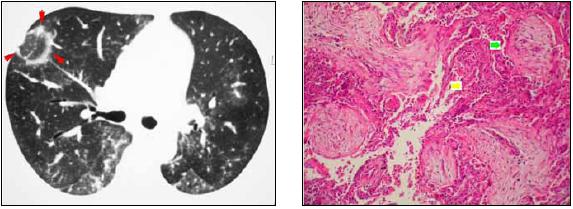

En la tomografía computarizada se evidenció una lesión nodular con densidad de "vidrio esmerilado" rodeada por un anillo de mayor densidad, asociada a áreas de aumento en la densidad del parénquima pulmonar con patrón en "vidrio esmerilado" y bronquios dilatados con pared engrosada. La biopsia pulmonar demostró pólipos de tejido fibroso en el espacio aéreo distal (flecha verde) e infiltrado intersticial crónico inflamatorio (flecha amarilla). Estos hallazgos son compatibles con el patrón histopatológico de neumonía de organización. Sin causa conocida, ni un contexto clínico específico asociado, se diagnosticó neumonía criptogénica de organización.

La sociedad Fleishner define el signo del halo reverso como un área focal redondeada con densidad de "vidrio esmerilado", rodeada por un anillo más o menos completo de consolidación. Este signo fue descrito inicialmente en pacientes con neumonía criptogénica de organización por Voloudaki (1) y Kim (2).